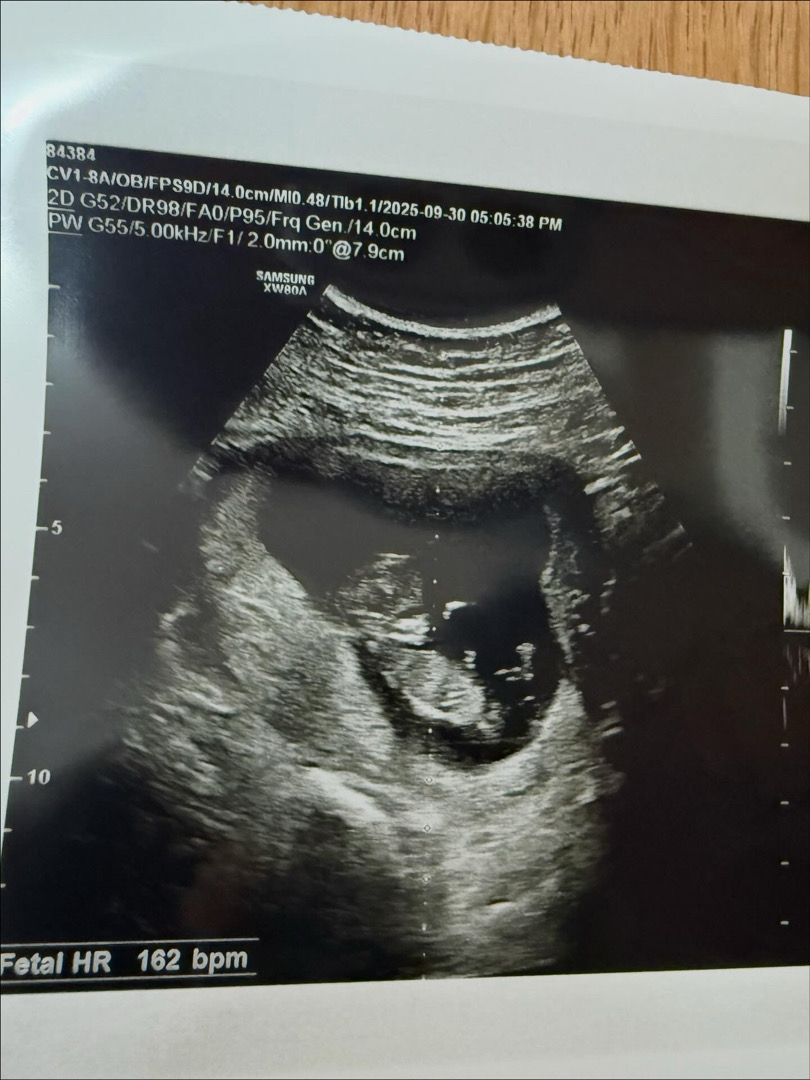

초음파슨배님들 알려주세요!!

지금 13주차인데 아직 당연히 안보이지만 너무 궁금해요 저희 아기는 왕자님일까요? 공주님일까요??